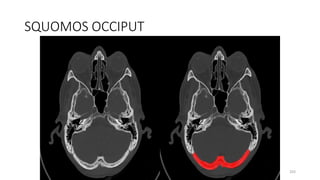

SQUOMOS OCCIPUT

SQUAMO OCCIPUT

SQUAMOUS OCCIPITO

SQUAMO- OCCIPITO